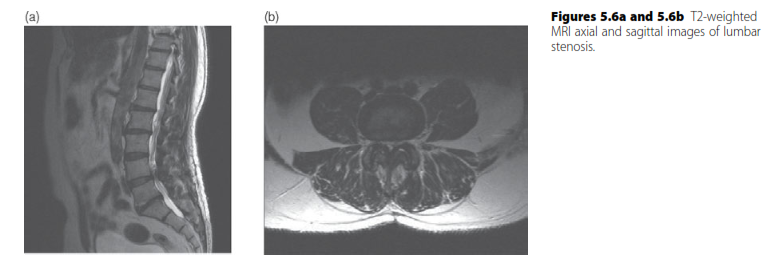

MRI of the lumbar spine is the gold standard imaging study for diagnosing lumbar spinal stenosis. It provides excellent visualization of soft tissues, including the neural elements, ligamentum flavum, disc bulges, and allows for accurate assessment of the spinal canal and neural foramina narrowing. Plain radiographs (Option A) can show degenerative changes but not soft tissue compression. CT (Option B) is good for bone but inferior to MRI for neural structures unless MRI is contraindicated. EMG/NCS (Option D) and epidural injections (Option E) are diagnostic/therapeutic adjuncts, not primary imaging modalities for initial diagnosis.

While exact thresholds can vary slightly, a sagittal diameter of the lumbar spinal canal less than 10 mm is generally considered absolute stenosis, and 10-12 mm is considered relative stenosis. Values greater than 12 mm are typically considered normal. Therefore, 'less than 10 mm' (Option C) represents absolute stenosis.